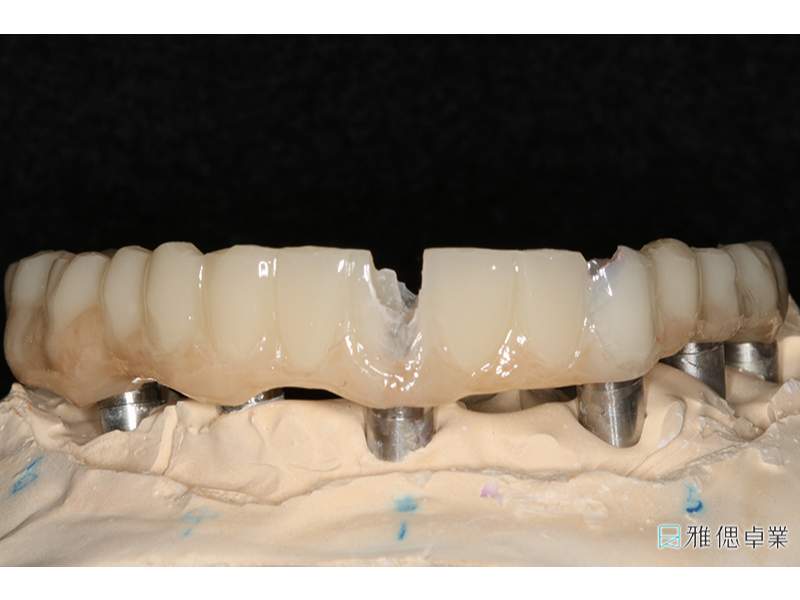

精密設計基座上的正式假牙

基座上每顆正式假牙皆是單獨的,方便清潔與維修